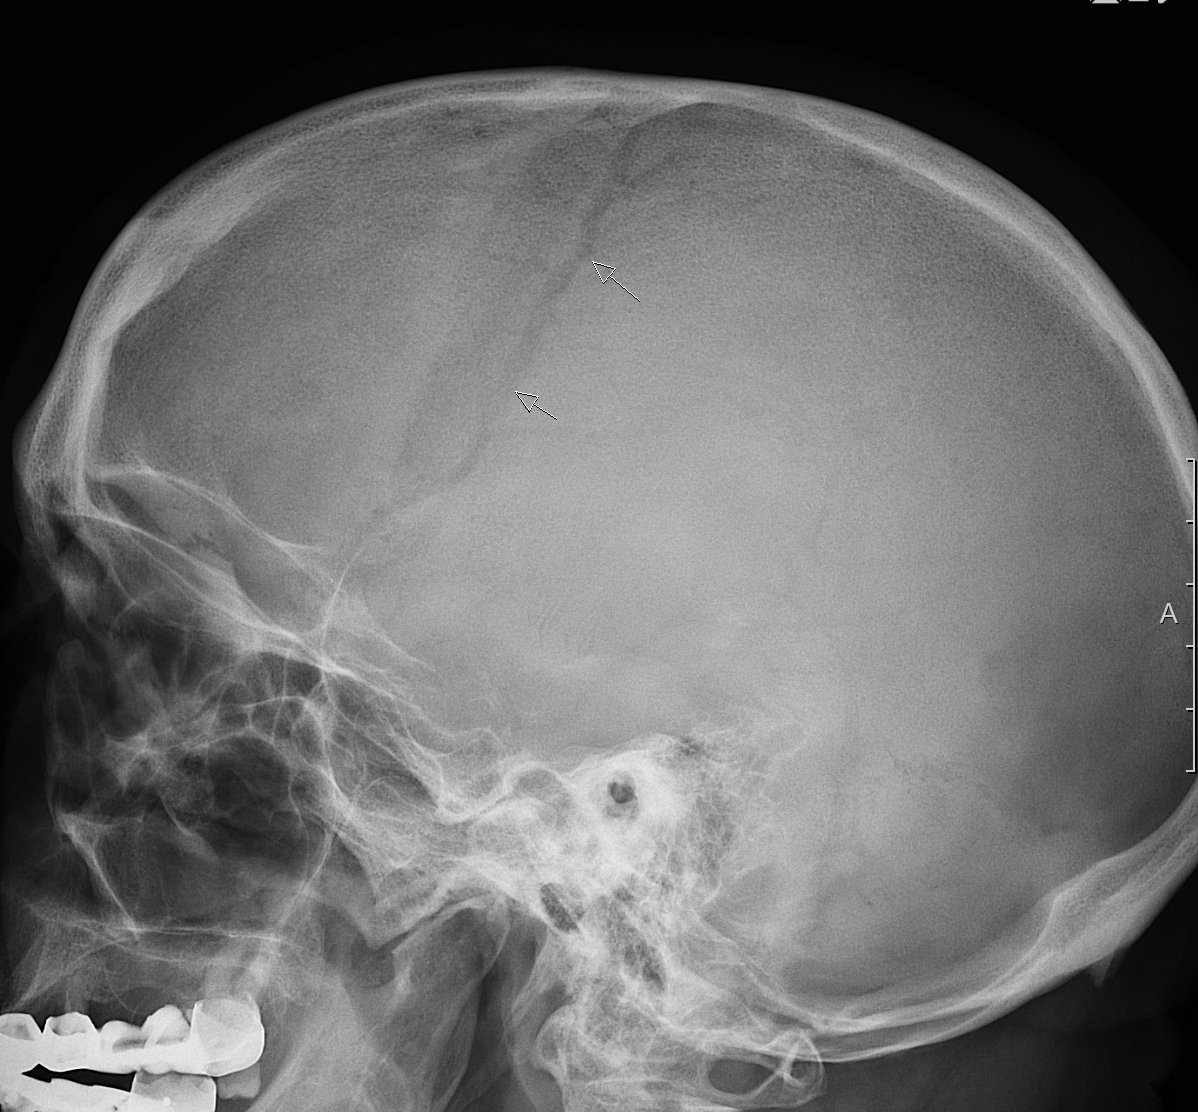

Пациент, 21 год, травма левой половины черепа в области теменной кости. Кратковременная потеря сознания, рвота.

Тип: Клиническое наблюдение

Область: Череп и головной мозг

Модальность: Rg

Дата: 11.03.2021 - 21:39